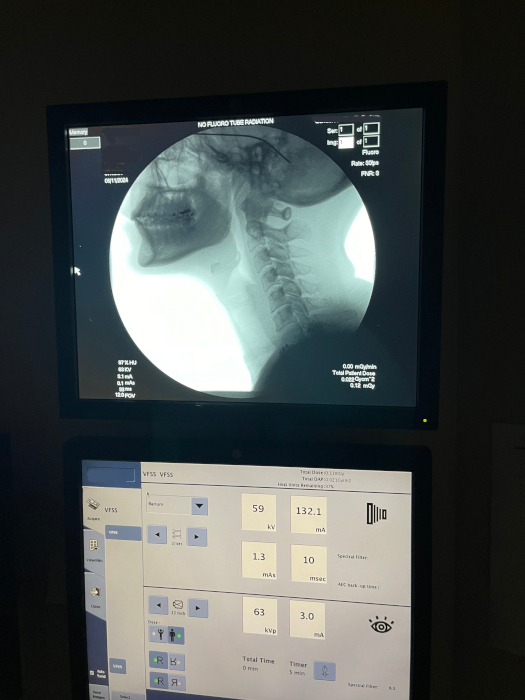

Mom at her test.

Here is what they were looking at.